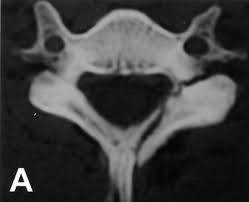

The transverse foramen is an opening on each of the transverse processes of the cervical spine which gives passage to the vertebral artery and vein and a sympathetic nerve plexus. There are two transverse processes that extend off each vertebra in the details: Transverse process fractures are common sequelae of trauma, although they are considered a minor and stable lumbar spine fracture. Transverse processes are typically fractured in direct blows from athletics touch or impact from falls from bikes/motorbikes or by heights. However, postmortem computed tomography (pmct) has made detection of this type of injury easy. There are two transverse processes that extend off each vertebra in the spine, one on each side. A transverse process fracture is a break in 1 or more transverse process. In 78% of transverse process fractures, ct scanning showed that the fracture extended into the transverse foramen. A transverse process fracture is considered as a rare injury. A transverse process fracture is a break in 1 or more transverse process. What is a transverse process fracture? Transverse process fractures caused by stress are likely under detected since even an acute transverse process fracture requires a high index of suspicion to be correctly identified(4,7). If ct confirms isolated injury lateral flexion/extension views are indicated to rule out dynamic instability.

However, postmortem computed tomography (pmct) has made detection of this type of injury easy. There are two transverse processes that extend off each vertebra in the details: What is a transverse process fracture? It may occur as an avulsion fracture due to strong contracture of the muscles. It occurs as a result of sudden and extreme trauma. If ct confirms isolated injury lateral flexion/extension views are indicated to rule out dynamic instability. Vertebral angiography, performed in eight patients with fractures involving the transverse foramen, showed dissection or occlusion of the vertebral artery in seven (88%) instances. This part extends out from the side of the main body of the bone (called the vertebral body). A transverse process fracture at the level of l5 is a surrogate marker of vertical instability of the pelvic fracture due to the attachment of the iliolumbar ligaments. We retrospectively reviewed the reports of lumbar spine and abdominopelvic ct scans from 2017 and 2018 to classify the types of spine fractures, their mechanism of injury, treatment and. Up to 60% of lumbar transverse process fractures identified on ct will be missed on plain radiographs. In 78% of transverse process fractures, ct scanning showed that the fracture extended into the transverse foramen. Transverse process fractures identified on helical computed tomography (ct) scans without the presence of any other fracture or.